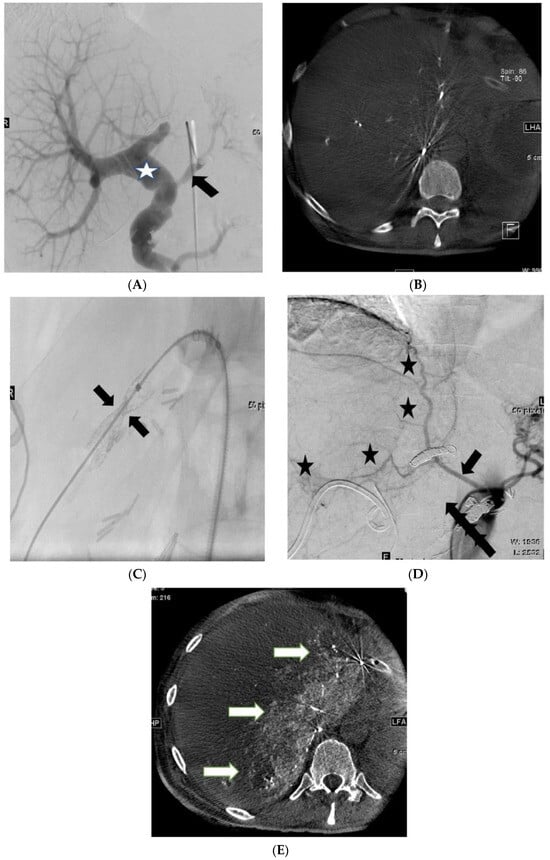

2. Methods and Results

Patient Information